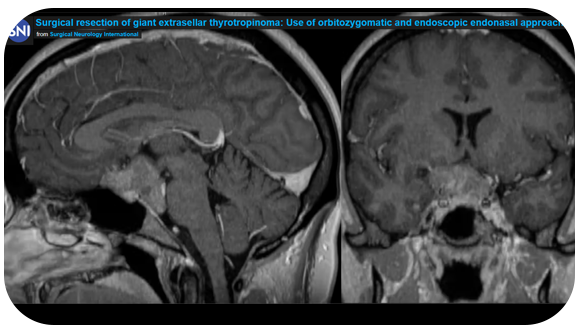

Surgical Resection of Giant Extrasellar Thyrotropinoma